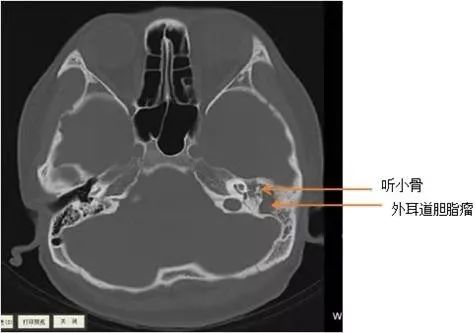

为明确诊断,梅医生又为徐大伯开出了螺旋CT检查,结果显示大伯的右侧外耳道骨壁、乳突区及听小骨骨质均被破坏、吸收,这些症状可能就是胆脂瘤破坏听小骨的传导功能而引发听力下降,又侵犯到面神经引起的面瘫的结果,如果再不及时进行干预,侵犯入脑就会引发生命危险。

ct片

“你先别哭呀,胆脂瘤并不是真正的肿瘤,可以手术除去的。”苏立众主任忙安慰泪眼婆娑的小林别紧张,并简单介绍此少见疾病的来龙去脉,然后开具了颞骨CT检查。

不出所料,颞骨CT检查显示小林左侧外耳道胆脂瘤,已挤压破坏左侧听骨链,且与左侧颈静脉及面神经管等重要结构关系密切,所以小林疼痛症状明显,左耳听力已有明显的下降。一切明了,小林如释重负。